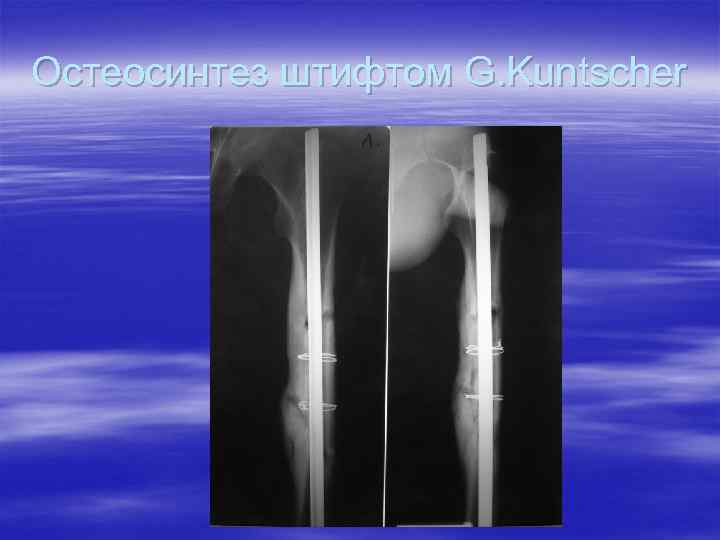

Остеосинтез штифтом G. Kuntscher